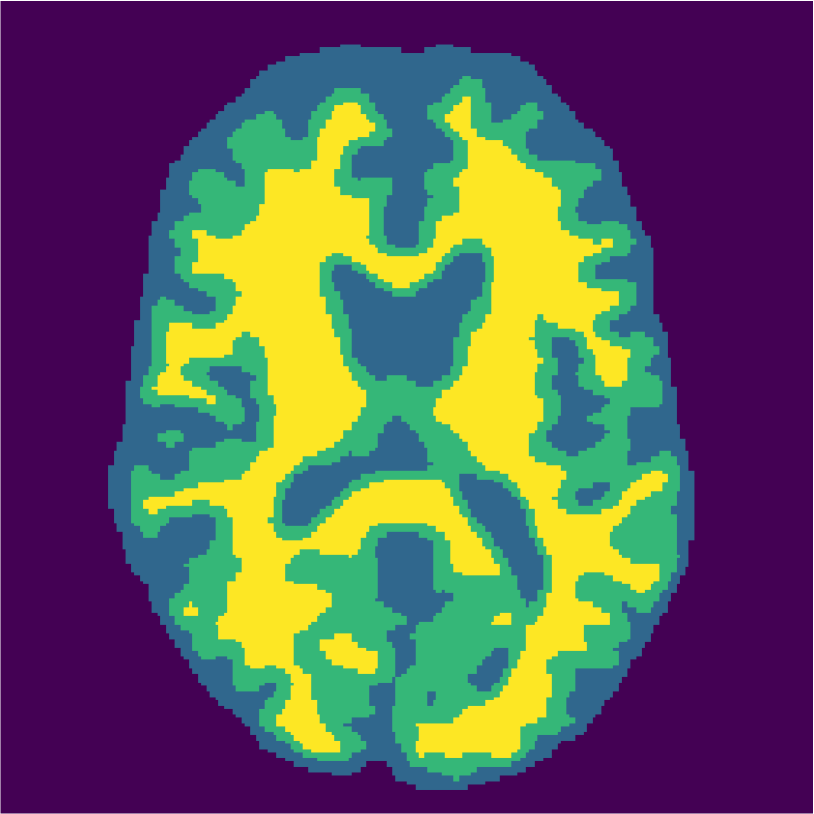

Examples of the segmentation results on one of the target test images are shown in Figure 8 for experiment 2.1, Figure 9 for experiment 2.2, and Figure 10 for experiment 2.3. Examples are shown after using 1 target patch per tissue for training, and after using 100 target patches per tissue for training. The results show that only the mrai-net classifier is able to predict a segmentation that approaches the ground truth with only 1 target patch per tissue for training (error for experiment 2.1 = 0.269, experiment 2.2 = 0.403, experiment 2.3 = 0.320), while the source and target classifiers cannot (source error for experiment 2.1 = 0.667, experiment 2.2 = 0.653, experiment 2.3 = 0.435; target error for experiment 2.1: 0.591, experiment 2.2: 0.614, experiment 2.3 = 0.596). After using 100 patches the source and target classifiers can predict a gross segmentation of WM, GM and CSF (source error for experiment 2.1 = 0.213, experiment 2.2 = 0.384, experiment 2.3 = 0.363; target error for experiment 2.1: 0.205, experiment 2.2: 0.368, experiment 2.3 = 0.368), but the mrai-net classifier prediction shows more details and a lower tissue classification error (error for experiment 2.1 = 0.111, experiment 2.2 = 0.276, experiment 2.3 = 0.284).